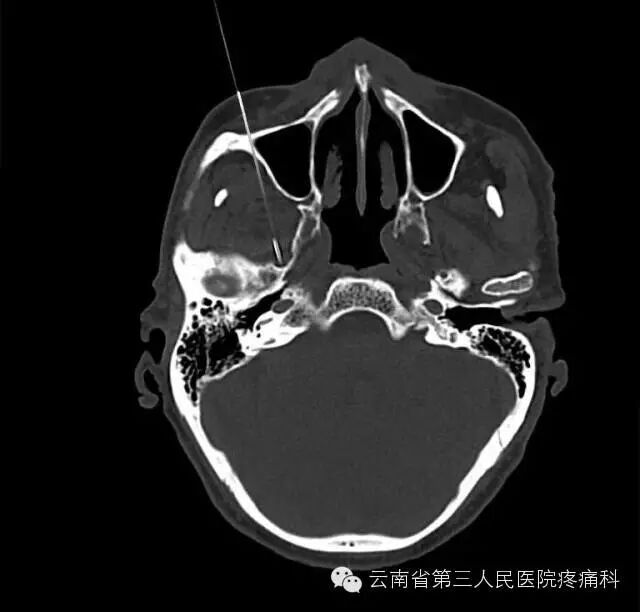

我科熟练开展经卵圆孔半月神经节射频热凝治疗

经皮穿刺半月神经节射频热凝术是治疗三叉神经痛最有效方法之一

治疗原理:三叉神经为感觉神经,其中神经纤维(AA纤维和AB纤维)能耐受较高温度,而痛觉神经纤维不能耐高温,CT引导三叉神经热凝术选择破坏痛觉纤维,使患者疼痛治愈。

治疗优势:安全、疗效好、不易复发、无副作用、费用比手术治疗低、创伤小、痛苦小、治疗时间短。

此项技术的重要环节在于靶点穿刺的准确性,利用CT引导或3维重建技术,可以使穿刺成功率和有效性大大提高。证疗效及安全的另一重要环节为热凝温度选择科学性。